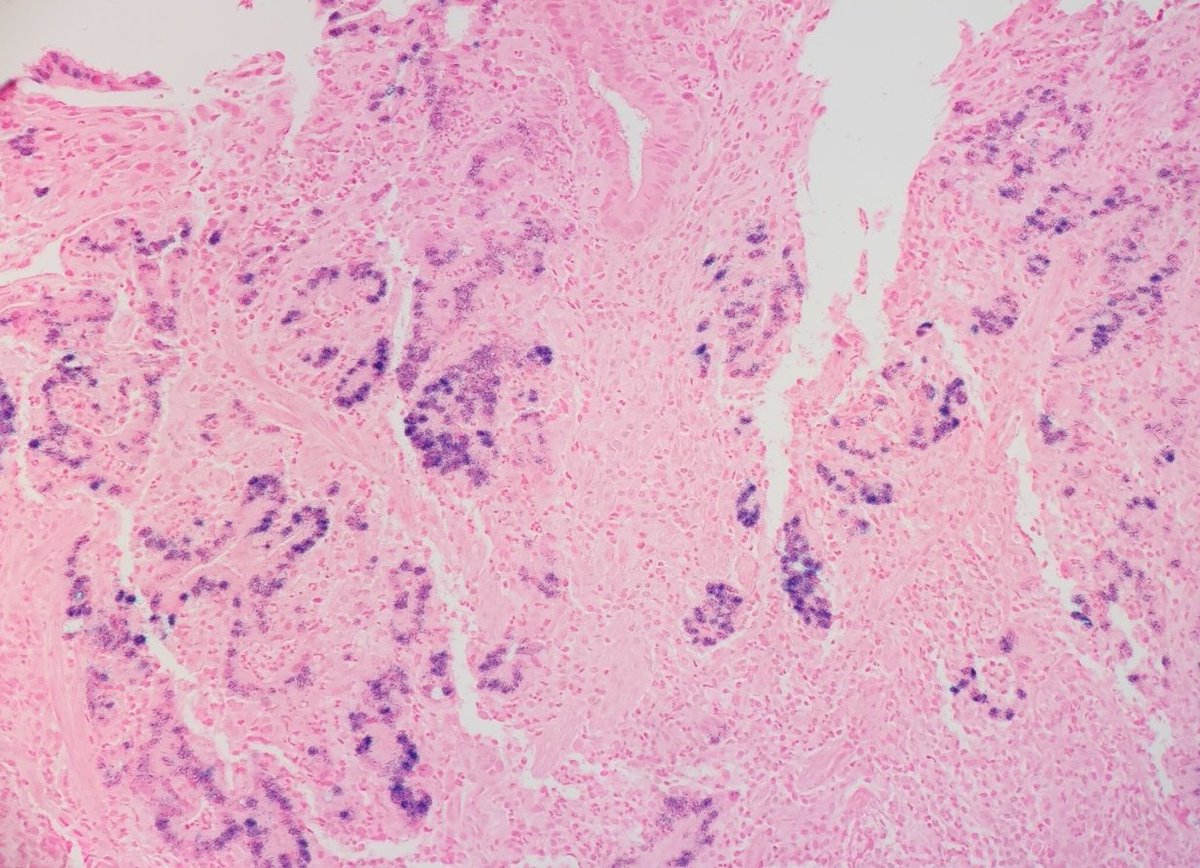

Total gastrectomy from pt with CDH1 germline mutation. 🦅👀 Courtesy of Dr. Dipti Karamchandani. #pathology #GIpath #PathTwitter

Total gastrectomy from pt with CDH1 germline mutation.

🦅👀 Courtesy of Dr. Dipti Karamchandani.

#pathology #GIpath #PathTwitter